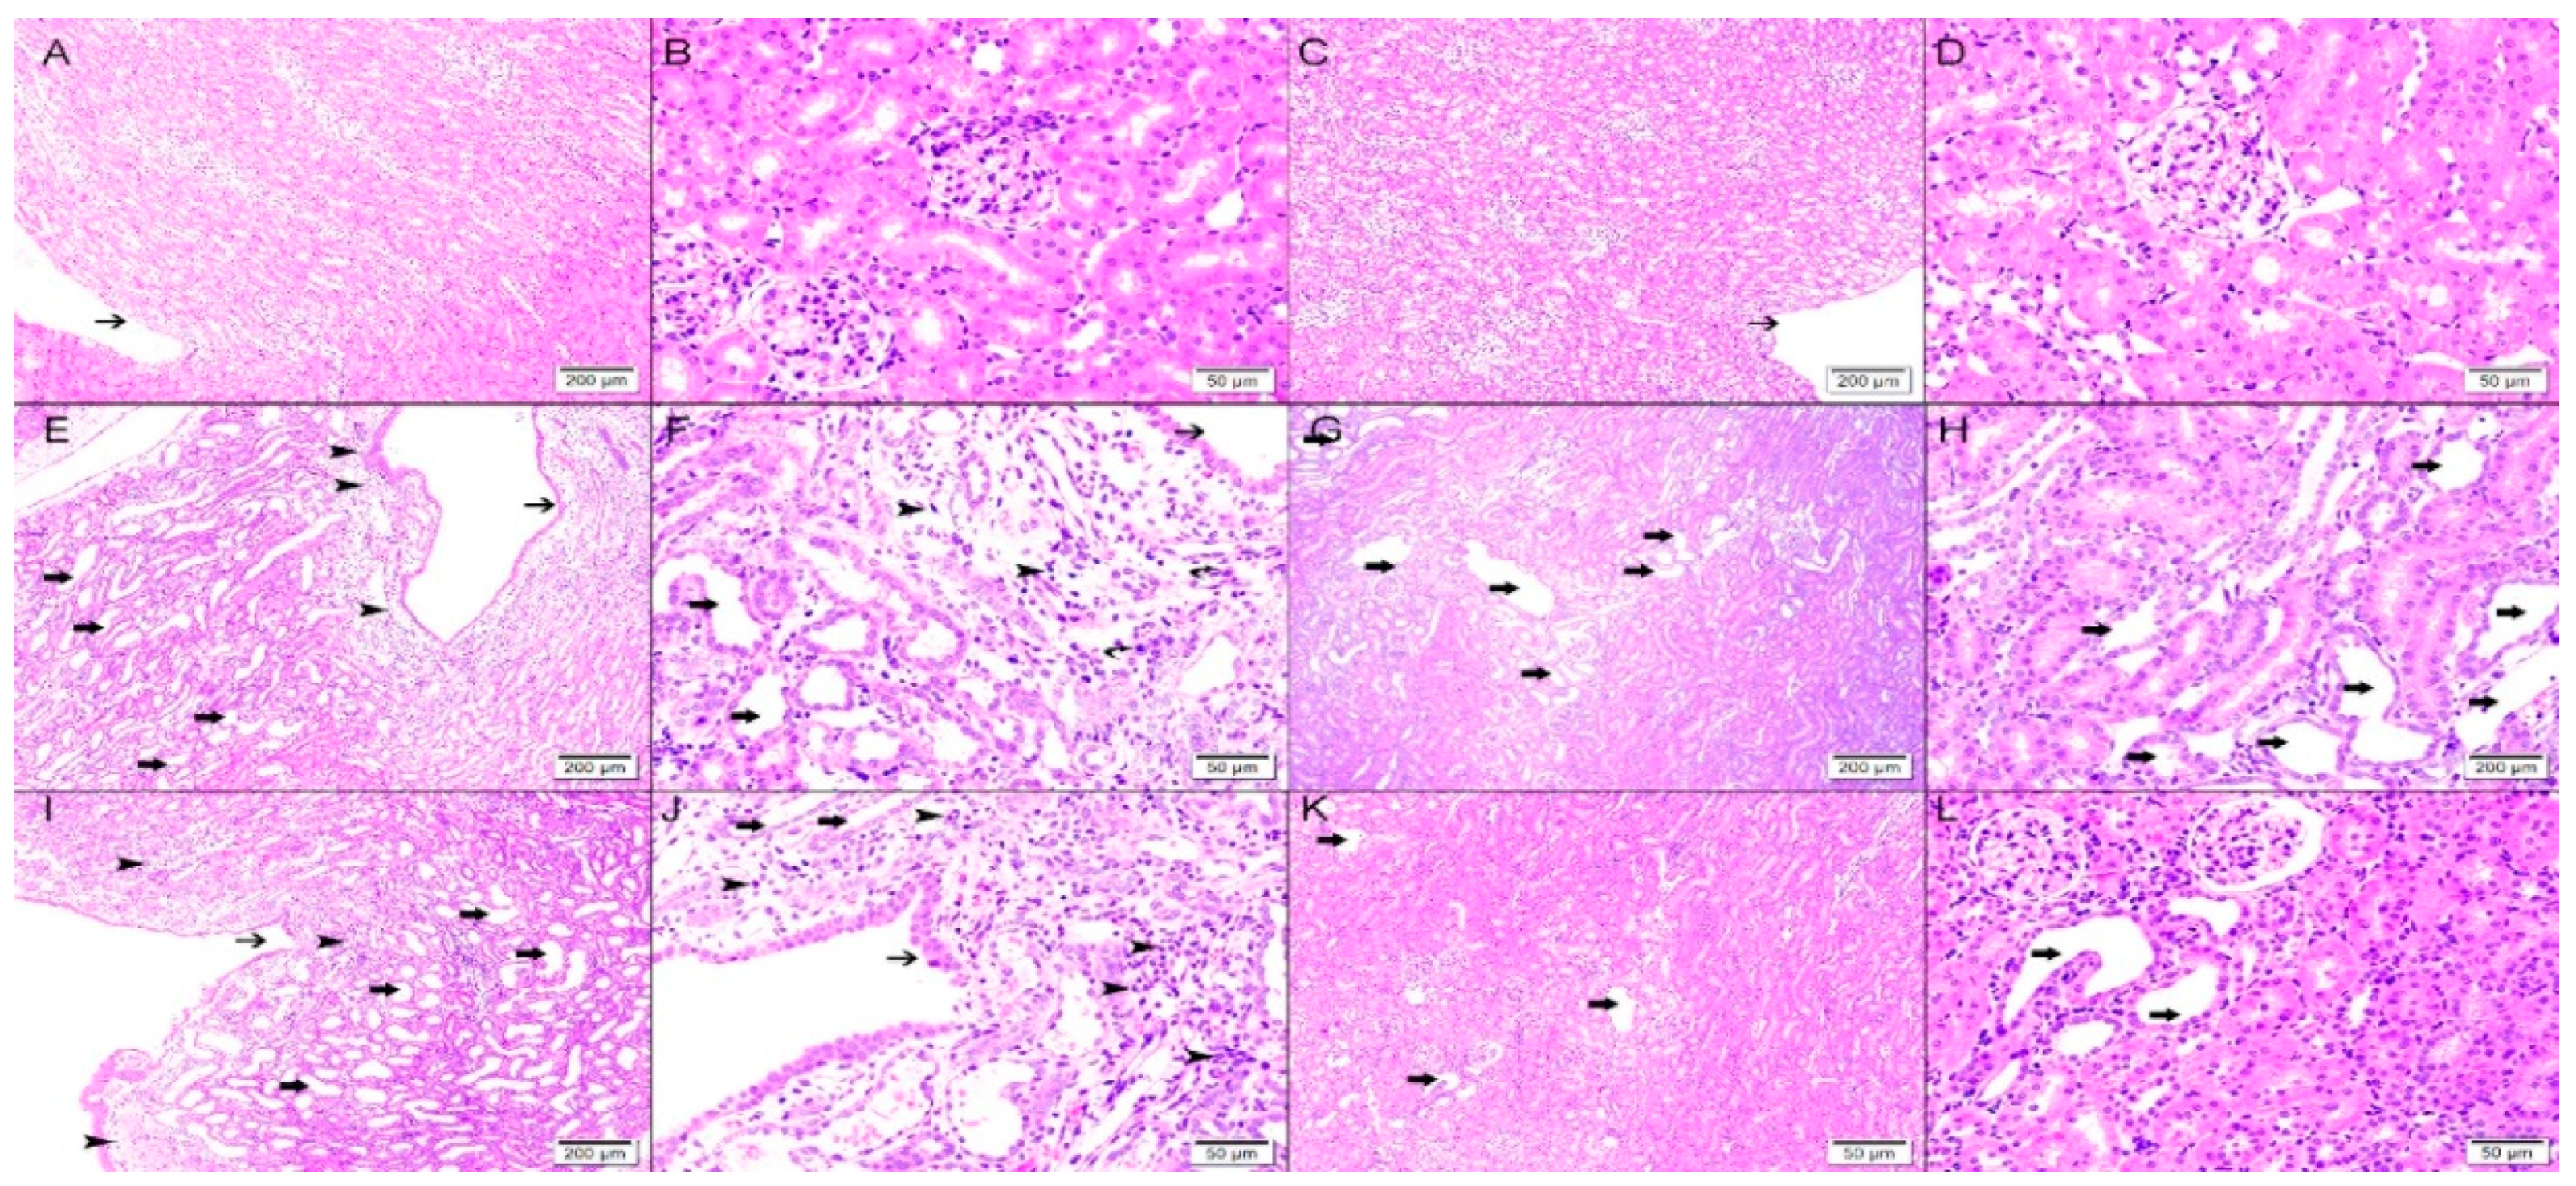

As demonstrated in Figure 6, three days after the creation of the obstruction, the control right kidney in Vx-1 and AG-1 showed normal kidney architecture and histology with 0% dilated tubules (Figure 7). In Vx-1, the left obstructed kidney showed collecting duct dilation in the renal papillae with dilated calices and mild infiltration of renal papillae interstitial tissue with inflammatory cells, mainly lymphocytes. The cortical and superficial medullary tissue showed large areas of tubular dilatation and the degree of tubular dilatation in this group was 82.9 ± 3.3% (Figure 7). In AG-1, the left obstructed kidney showed similar histological features to the left kidney in Vx-1, including the inflammatory cell infiltrate and extracellular matrix, but there was a significantly lower degree of tubular dilatation (59.9 ± 3.57%, p = 0.0003).

Six days post-reversal of the UUO, the left previously obstructed kidney in Vx-2 had similar findings to the left kidney in Vx-1 but the findings were less marked (Figure 8) and the overall percentage of tubular dilatation in this group was 29.3 ± 6.7% (p < 0.0001) compared to Vx-1 (Figure 7). In AG-2, the left previously obstructed kidney showed similar histological features to the left kidney in Vx-2 (Figure 8) and the overall percentage of tubular dilatation in this group was 26.1 ± 6.3% (p > 0.05) compared to Vx-2.

Figure 8. Histological features in the right non-obstructed and left obstructed kidneys six days post-UUO reversal in both Vx-2 and AG-2. Upper panel (right nonobstructed kidneys): (A,B), right kidney in Vx-2 showing normal kidney architecture and histology with no dilated tubules with normal calices (thin arrow); (C,D), right kidney in AG-2 with normal kidney architecture and histology and no dilated tubules with normal calices (thin arrow). Middle panel (left kidney in Vx-2): (E,F), shows collecting ducts dilation (thin arrow) in renal papillary area with dilated calices (thick arrow) with mild inflammatory cells infiltration of the renal papillae interstitial tissue consisting of lymphocytes mainly (arrow head); (G,H), the cortical and superficial medullary tissues show focal tubular dilatation (thick arrow). Lower panel (left kidney in AG-2): (I,J) shows collecting ducts dilation (thin arrow) in renal papillary area with dilated calices (thick arrow) with mild inflammatory cells infiltration of the renal papillae interstitial tissue consisting of lymphocytes mainly (arrow head); (K,L), the cortical and superficial medullary tissue show focal tubular dilatation (thick arrow).